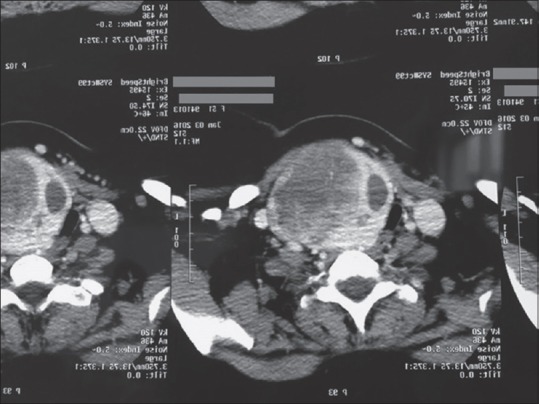

Aim: Tracheomalacia is a potentially life-threatening, but a rare complication of thyroidectomy. In previous studies, the incidence rate was very different. Considering the relatively high prevalence of goiter and thyroidectomy in the West Azerbaijan region, we designed this study to determine the tracheomalacia incidence in patients who underwent thyroidectomy within a 10-year interval.

Materials and methods: This retrospective study was done in Urmia Imam Khomeini Hospital in West Azarbayjan Province. Demographic characteristics including the age and sex of patients who underwent thyroidectomy between 2007 and 2017 and also the incidence of tracheomalacia after surgery were recorded.

Results: From 2007 to 2017, total 1236 thyroidectomy were performed. The patients' age ranged from 15 to 83-year-old with a mean age of patients was 44.5 ± 13.81 years old. Two hundred and twenty-nine patients (19%) were male and 1007 (81%) were female. We did not find any cases of tracheomalacia after thyroidectomy in our study population.

Conclusion: Based on the results of this study, it seems that with the necessary precautions, the incidence of tracheomalacia can reach zero.